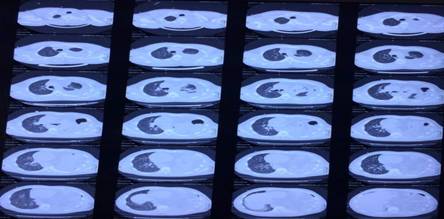

El resultado anterior se ratificó mediante la tomografía axial computarizada simple (Fig. 2) y contrastada de tórax (Fig. 3).

En este paciente los resultados de los estudios imagenológicos fueron determinantes para establecer el diagnóstico definitivo y la causa. Resulta válido destacar que este tipo de hernia se diagnostica inicialmente por el método clínico; sin embargo, el examen de elección es la radiografía de tórax, luego se ratifica mediante la tomografía axial computarizada simple y, por último, a través de la tomografía contrastada.1,4